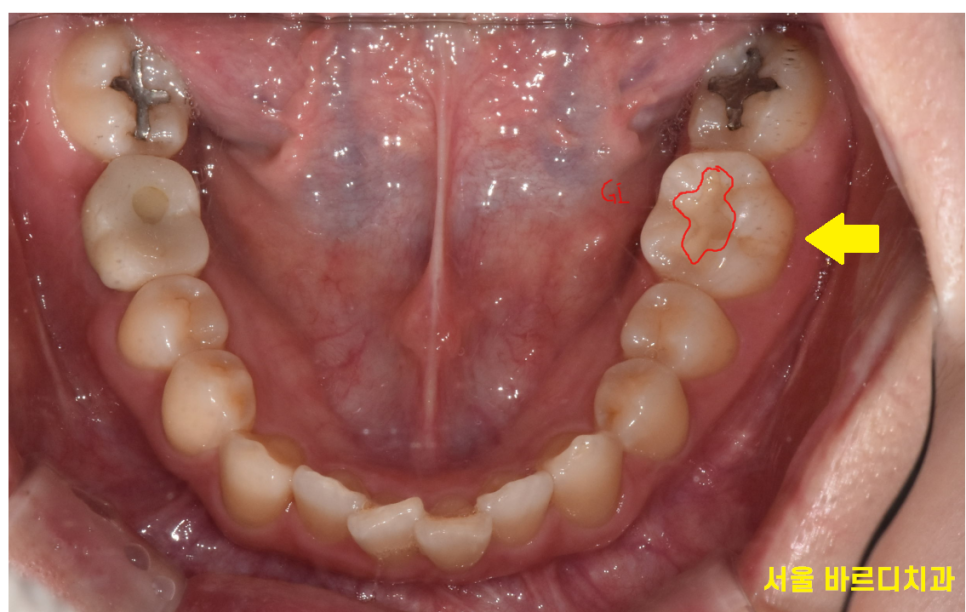

231209 임신중에 임시로 뗴워놓은 환자분